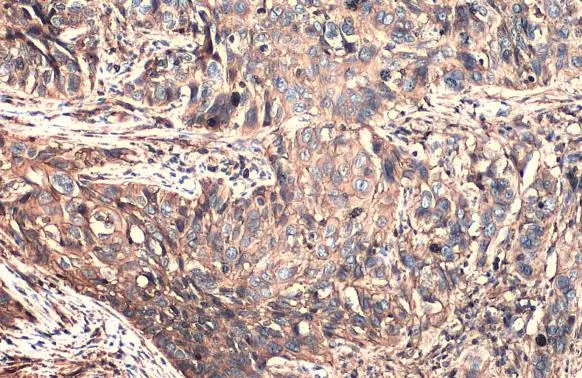

CD44 antibody

Cat. No. GTX102111

ApplicationsWB ICC/IF IHC-P IHC-Fr IP LCI

CD44 is an 82kDa multifunctional transmembrane glycoprotein involved in cell migration, proliferation, differentiation, and signaling pathways that mediate cell survival. It is involved in many malignancies as well as being recognized as a cancer stem cell marker. Importantly, it is expressed in leukocytes and is a marker of leukemia-initiating cells, being found to be critical in the pathogenesis of T cell acute lymphoblastic leukemia.